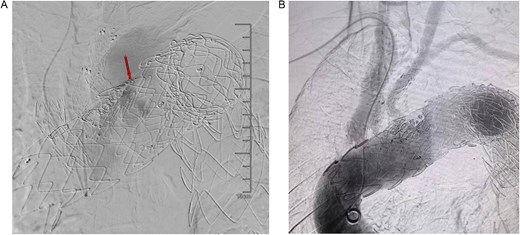

In November 2023, the patient had another recurrence of blood in the phlegm, and a CTA at an external hospital revealed extravasation around the thoracic aortic stent graft. And endoluminal embolization of the left bronchial artery was performed. Upon admission on December 1, 2023, symptoms had improved. It was hypothesized that the Gore aortic stent graft compressed the original subclavian artery BD stent graft, causing a type Ic endoleak (Fig. 7A). Left subclavian artery stent graft implantation and balloon dilation on December 4, 2023, improved the endoleak (Fig. 7B). However, the patient was readmitted on December 29, 2023, due to recurrent blood in phlegm, leading to transcatheter embolization of the right bronchial artery on January 3, 2024. Symptoms improved significantly, and the patient was discharged.

(A) It was hypothesized that the gore aortic stent graft compressed the original subclavian artery BD stent graft, causing a type Ic endoleak. (B) Left subclavian artery stent graft implantation and balloon dilation on December 4, 2023, improved the endoleak.